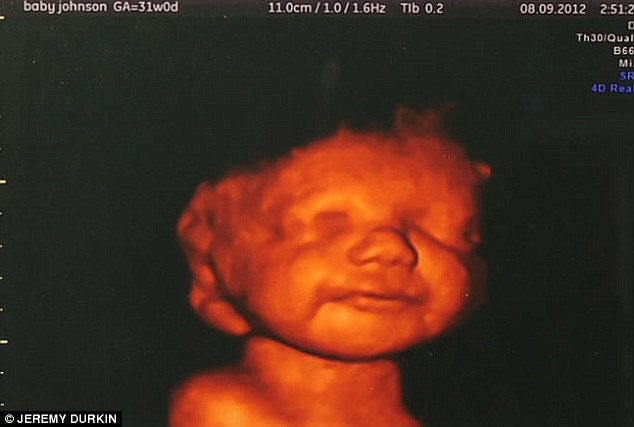

Padecía malformaciones cerebrales

Una ecografía en 3D convenció a la madre de Lucian de que no debía abortar (infoCatólica

17.01.2013)

El Daily Mail ha publicado un reportaje con la historia

de Katyia Rowe, que quedó «desoladada cuando le dijeron que su hijo padecía

tales malformaciones cerebrales que su vida sería muy corta». Le instaron a

que considerase acabar con el bebé. En una de las ecografías 3D, Katyia vio en

tiempo real cómo su hijo sonreía, hacía globitos, pateaba y gesticulaba con

los brazos. No pudo hacer otra cosa que lo que hizo, quererle y ponerle

nombre: Lucian